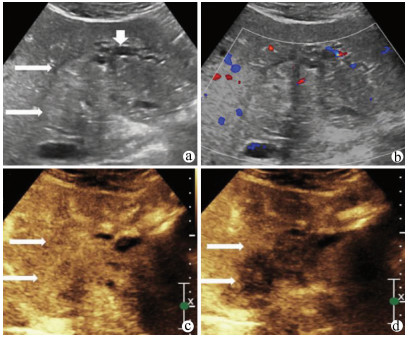

肝病超声诊断指南

中华医学会超声医学分会, 中国研究型医院学会肿瘤介入专业委员会, 国家卫生和健康委员会能力建设和继续教育中心超声医学专家委员会

2021, 37(8): 1770-1785. DOI: 10.3969/j.issn.1001-5256.2021.08.007

摘要(3138) HTML (6640) PDF (9311KB)(810)

超声检查无创、实时、价廉,无辐射、便于反复进行,是最常用的肝脏影像学检查方法。近年来,超声检查新技术如超声造影、弹性成像发展迅速,可有效鉴别肝内占位性病变性质、评估肝纤维化和门静脉高压程度以及监测肝病治疗效果,在临床肝病及其介入治疗中发挥重要诊断价值。本指南规范了肝病多模态超声技术(灰阶超声、彩色多普勒超声、超声造影、弹性超声)检查的仪器调置、患者准备及医生检查方法;对肝脏弥漫性病变(炎性病变、纤维化、硬化)、多种占位性病变及肝病介入操作的多模态超声技术诊断标准进行了定义和规范,同时推荐了超声监测周期及肝脏疾病超声诊断报告书写规范。